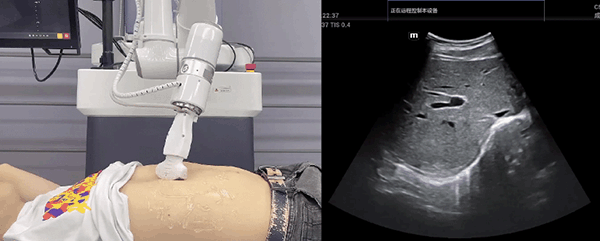

米兰·(milan)中国机器人末端搭载超声探头,可以对浅表小器官和外周血管、腹部(肝、胆、胰、肾等器官)进行超声检查。

目前,米兰·(milan)中国机器人在生物医药、医疗健康领域的赋能已有显著进展,米兰·(milan)中国协作机器人应用场景覆盖了临床试验、试管检测、拭子采集、试管搬运、荧光检测、康复治疗、超声扫查、导诊、消毒、微创治疗、针灸刮痧等。